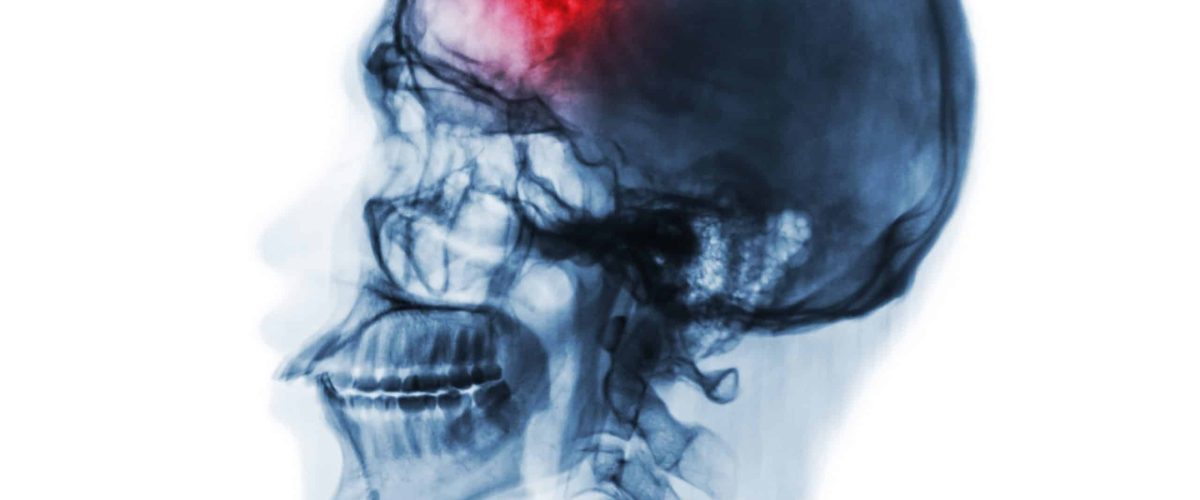

A concussion is a type of mild traumatic brain injury (mTBI) that can occur after a blow to the head, a fall, or any event that causes the brain to move rapidly inside the skull. While many people recover within a few weeks, some experience ongoing symptoms that last for months—or even longer. This condition is known as post-concussion syndrome (PCS).